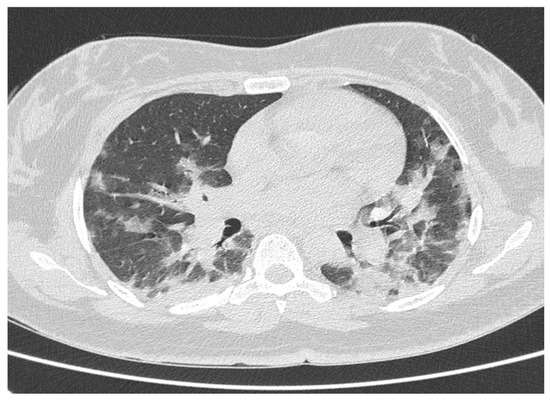

2.2. Chest HRCT Acquisition and Examination

3. Results